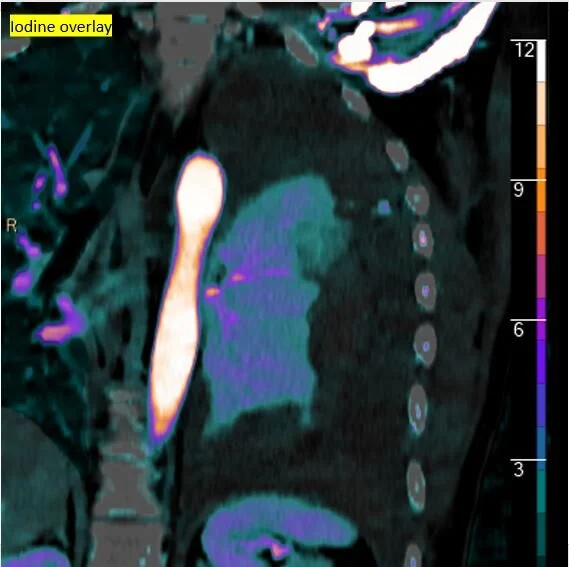

Something new for adrenal nodules